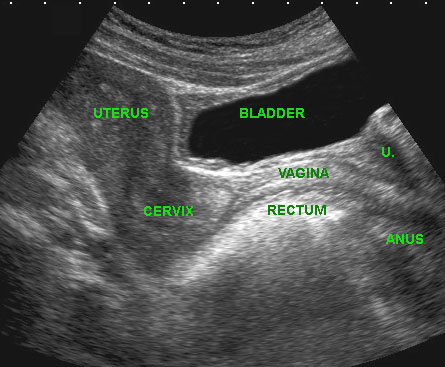

Trên mặt phẳng đứng dọc có thể xác định được tử cung, cổ tử cung, âm đạo, trực tràng hậu môn và niệu đạo (u.), cũng như túi cùng trước và túi cùng sau của âm đạo ở trạng thái xẹp.